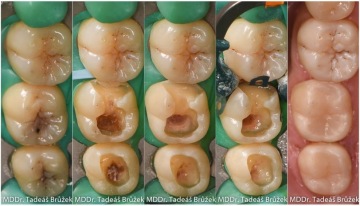

Postup zhotovení

Po znecitlivění zubu lékař odstraní zubní kaz a zbytky stávajících výplní. Zahladí všechny okraje preparace a zub izoluje od dutiny ústní pomocí kofferdamu - "blány", která umožní aplikovat fotokompozitní plombu v suchém prostředí. Pouze tak je možné zajistit ideální vlastnosti a životnost plomby. Pokud je kaz v mezizubním prostoru, lékař zub dostavuje s pomocí matrice utěsněné klínkem, aby výplňový materiál přesně přiléhal k okraji zubu.

Následuje aplikace adhezivního systému a modelace výplně tak, aby odpovídala tvaru přirozeného zubu. V průměru trvá celý tento proces kolem 1 hodiny. Během jedné dvouhodinové návštěvy lze ošetřit 2 až 4 sousedící zuby. Při odstranění kazu a aplikaci výplně je vhodné použití zvětšení (dentální mikroskop, lupové brýle), které umožní přesnější práci.